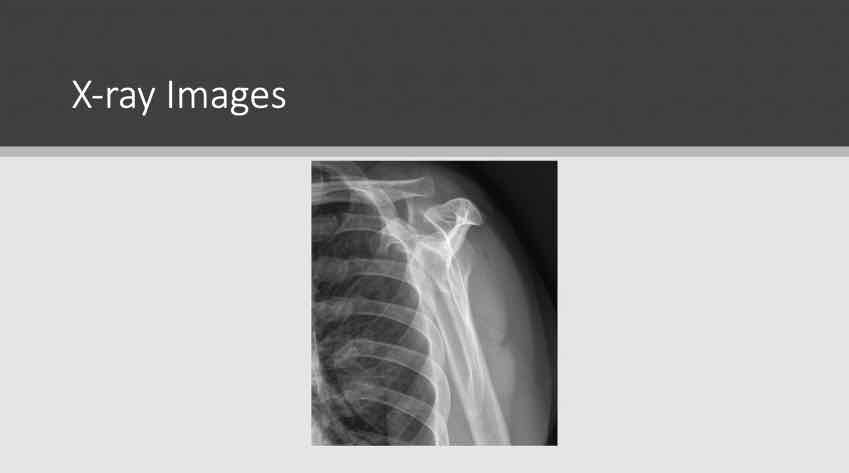

Arthroskopische Therapie glenohumeraler Knorpeldefekte J. Theopold

Sekundäre Prävention: Welchen Einfluss haben RM-Defekte, SLAP-Läsion und Instabilität auf die Arthroseentwicklung? D. Berthold

Operative Therapie der manifesten Omarthrose M. Farkhondeh Fal

Die verschiedenen konservativen und operativen Behandlungsmöglichkeiten der Schulterarthrose kennen zu lernen und ihre jeweiligen Indikationen zu verstehen

Die Bedeutung von Rotatorenmanschetten-Defekten, SLAP-Läsionen und Instabilität für die Entwicklung von Schulterarthrose zu erklären